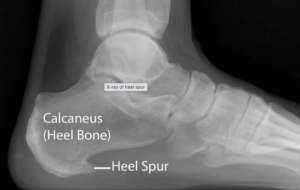

Comment: My Plantar Fasciitis pain is caused by my heel spur.

MYTH – A heel spur is a calcium deposit that forms as a bony protrusion from the undersurface of your heel bone. Often these are painless and are often caused by repetitive trauma or stretching of the plantar fascia as well as the membrane that covers the heel bone. This process usually occurs over many months. Repetitive trauma is the excessive load the foot is placed under. Here we see the irritation to the plantar fascia coming 1st, and the subsequent development of the heel spur 2nd.

Fun Fact: It is of interest that only about 5% of the population that has a heel spur experience pain!*